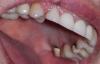

Bukasha Опубликовано 24 мая, 2011 Поделиться Опубликовано 24 мая, 2011 Здравствуйте.Неск. дней назад мне поставили восемь коронок мк на постоянный цемент. И я увидела, что внутри на всех коронках темные полоски. Для меня это стало сюрпризом, честно говоря. Врач сказал, что изнутри не видно. Видно конечно, ещё как, особенно если учесть, что по роду работы у меня часто и широко открыт рот, причем при большом количестве людей. И у коллег многих видно всё-всё во рту. Вобщем понятно, что эстетика не айс. Я узнала из инета, что это называется "гирлянда". И что есть ещё такая "плечевая масса". А теперь собственно вопрос: зачем это сделано, можно ли (было) избежать, как оцениваются такие коронки: как гирлянды или как с плечевой массой, если со стороны щек у них нет темных полосок, а со второй стороны есть. Я нашла тут тему о похожем, но честно - не поняла из ответов врачей, зачем нужны эти гирлянды. Для здоровья ли дёсен, для экономии средств пациента, для экономии времени техника или это сложная технология - выводить плечевые массы? Если десна поднимется "с годами" и станет серой, так там уже чЁрно!))...Я в глубоких раздумьях. Ссылка на комментарий

Bukasha Опубликовано 31 мая, 2011 Автор Поделиться Опубликовано 31 мая, 2011 (изменено) Делаю гирлянду практически всегда,единственное,предупреждаю заранее.Альтернатива-светлая гирлянда на коронках из оксида циркония с ценником ,начинающимся от 20 тысяч за коронку в зависимости от региона (ну и до 60 ).Под плечевую массу обтачивать зуб по кругу бывает просто невозможно,столько тканей твёрдых просто нет,ну или негуманно,чем больше останется зуба,тем лучше ретенция(удержание) коронки,эстетика эстетикой,ну и функция должна быть обеспечена ,вы же жуёте коронками ,не только улыбаетесь,а нагрузка колоссальная при жевании,не забывайте,тысячи циклов жевательных она обязана вам обеспечить.В общем ,не знаю,что надо делать на работе,чтобы коллеги увидели гирлянду на молярах,уж извините. Сцена, софиты, хор, солисты... Оперный театр. Зрителям не видно, коллегам видно. Смотрите, на втором фото никаких расширителей, просто открыла рот, запрокинула слегка голову, муж сфоткал со вспышкой. Ладно, это уже, оказывается, полбеды. Вы очень нужный вопрос затронули, про тысячи жевательных циклов. Новую тему наверное не надо мне создавать, здесь расскажу. Я не могу жевать на одной стороне. Точнее, мне тяжело это делать, как будто там не хватает высоты. Сегодня была на проверке-коррекции, бумажечками синеньками мне показывали, что "контакт есть, всё хорошо". А мне - нехорошо...(( Обыкновенный ужин вызывает усталость, как будто челюсти ходили в тренажерный зал. Если пища справа - нормально, если слева - как будто перетираю её. Три раза он мне этот мост (5-6-7) переделывал в общей сложности. Когда первый раз пожаловалась на неполный контакт - переделал ещё ниже, даже визуально было заметно, сам согласился. И я с ними долго ходила, пока другими зубами занималась, как с времянками... А контакт сегодня синей краской был не по всей шестёрке (меня она беспокоит больше всего ), а как-то по диагонали. Как самой проверить? Или не самой, но объективно? Я уже сходила к ортодонту в гос. клинику, он видел и предыдущую заниженную работу. Сказал - теперь есть контакт, хороший везде. А я как тупая мельница чувствую себя. Там даже форма какая-то допотопная по жевательной поверхности: плоские лепешки со вмятинками. Что делать?.. Изменено 31 мая, 2011 пользователем Bukasha Ссылка на комментарий